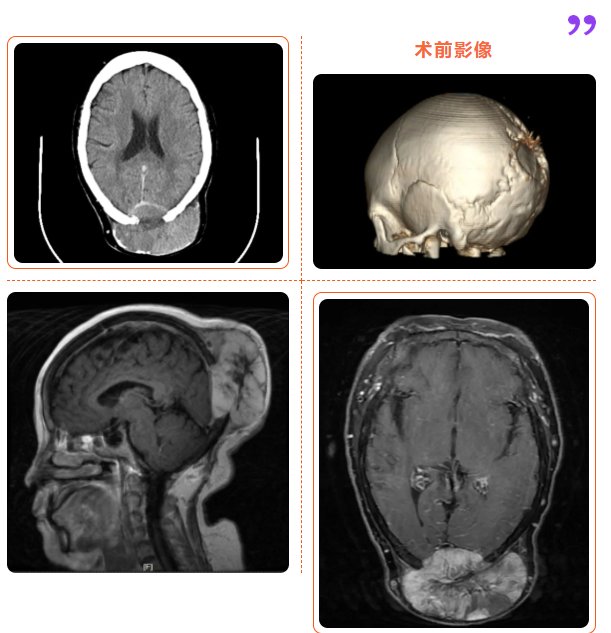

本着尽可能切除肿瘤,延长患者生命周期,提高患者生存质量的考虑,我院神经外科团队反复研究有效治疗这一复杂性颅内外沟通性枕部巨大肿物的治疗方案,经过数次研究讨论,多次术前三维模拟及实战模拟,在取得病人及家属同意后,行座位局麻下枕部肿块切除术+缺损颅骨修补术。手术历时2小时余,成功将患者枕部巨大肿物全部切除。手术结束后,患者安全送回病房,6小时后,复查术区CT未见明显出血,患者四肢也慢慢开始自主活动起来,未出现任何新发神经功能障碍。术后经术区局部放疗,进一步抑制肿瘤生长,治疗后3个月,患者再次来院复查,恢复状况良好,未发现肿瘤复发迹象。